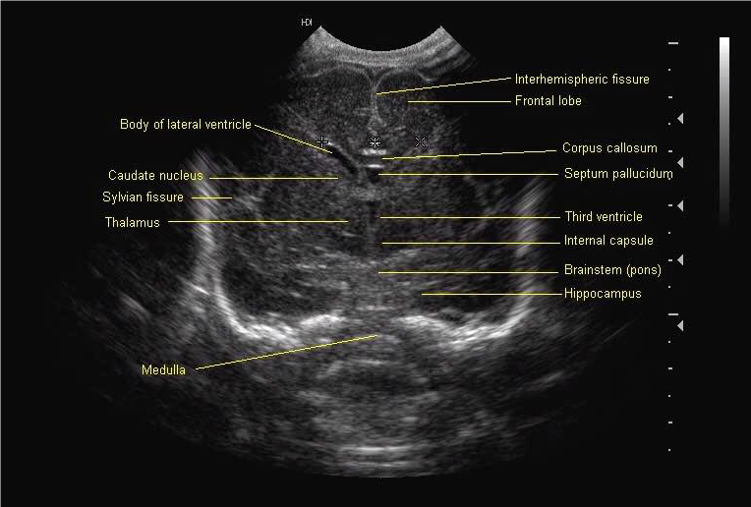

Standard views for cranial ultrasonography of the newborn

Mid Coronal